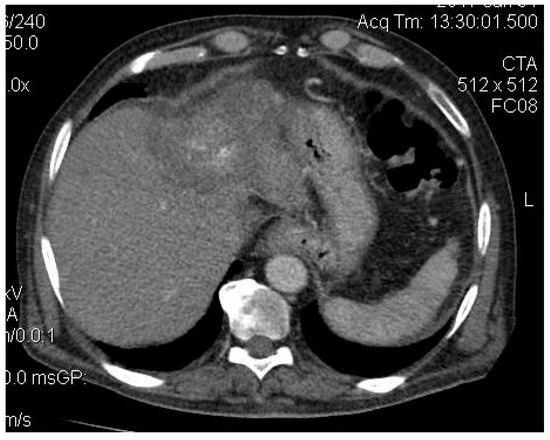

2. Case Presentation